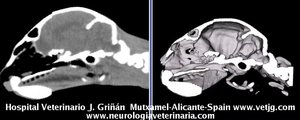

Mismo paciente: Correspondencias entre el corte sagital y el volumen, ambos reconstruidos a partir de imágenes TC (transversales) |